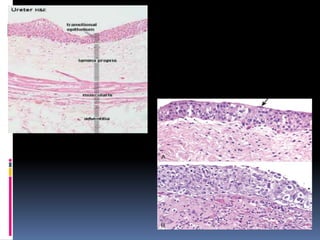

Normal Histology

 The mucosal surface of the renal pelvis, ureters,

urinary bladder, and urethra is lined by a

multilayered epithelium.

 The most superficial of which consists of

“umbrella cells”.

 This epithelial lining has historically been called

“transitional epithelium,” it is currently

preferentially referred to as urothelium.

 The wall of the urinary bladder is formed of four

layers: (a) epithelium (urothelium), (b) lamina

propria, (c) muscularis propria, and (d) adventitia